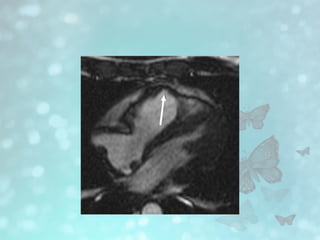

• #17 True fast imaging with steady-state precession image shows aneurysm formation of right ventricular wall (arrow)